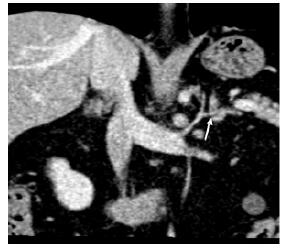

结果  以MIP或MPR技术评价图像质量, 左肾上腺静脉97例(97%)为1级, 1例(1%)为2级, 2例(2%)为3级; 右肾上腺静脉52例(52%)为1级, 19例(19%)为2级, 29(29%)例为3级。左肾上腺静脉均为1支; 91%与膈下静脉汇合后汇入左肾静脉; 左肾上腺静脉平均直径(3.6±0.6)mm(2.4~4.5 mm); 左肾上腺静脉与左肾静脉形成交角, 平均为(121.9±16.0)°(150~58°)。2例发现右侧双支肾上腺静脉; 67例(94%)右肾上腺静脉汇入下腔静脉, 4例(6%)汇入右副肝静脉; 右肾上腺静脉平均直径(3.2±0.5)mm(1.9~4.0 mm); 右肾上腺静脉与下腔静脉形成交角, 平均为(75.3±16.6)°(90~35°)。

Results  In the evaluation of image quality with MIP or MPR images, the left adrenal vein was excellent in 97% patients, sufficient in 1%, and non-diagnostic in 2%. For the right adrenal vein, 52% were excellent, 19% were sufficient, and 29% were non-diagnostic. The left adrenal vein was always a single one, 91% of which joined the inferior phrenic vein and then drained into the left renal vein. The diameter of the left adrenal vein ranged 2.4 mm to 4.5 mm (mean:3.6±0.6 mm). The angle of the left adrenal vein and left renal vein ranged 150° to 58° (mean:121.9±16.0°). Two patients were found to have double right adrenal veins. The right adrenal vein drained into the IVC in 67 of 71 patients (94%) and into the right accessory hepatic vein in 4 patients (6%). The average diameter of the right adrenal vein ranged 1.9 mm to 4.0 mm (mean:3.2±0.5 mm). The angle of the right adrenal vein and IVC ranged 90° to 35° (mean:75.3±16.6°).